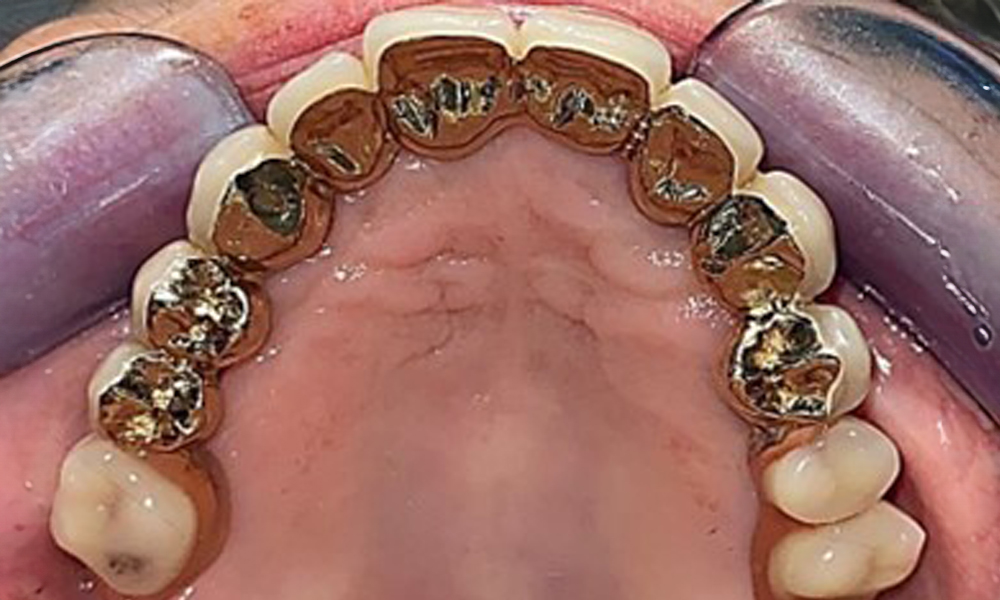

Occlusal view: Maxilla with removable, palateless denture.

Fig. 3: Occlusal view: Maxilla with removable, palateless denture.

The patient was fitted with a combined removable maxillary telescopic prosthesis more than 25 years ago (Fig. 1, Fig. 2, Fig. 3) and is very happy with her dentures. The patient has an adequate fixed denture for the mandible (Fig. 4).

The intraoral mucosa must be examined for possible fungal infections and pressure spots. The dentures must be visually inspected for cleanliness. The present case presented with interdental discolouration, attributed to tea consumption (Fig. 7). The dentures should be professionally cleaned in the dental practice using disinfection and cleaning baths.

Basal view of the dentures for assessing cleanliness.

Fig. 7: Basal view of the dentures for assessing cleanliness.